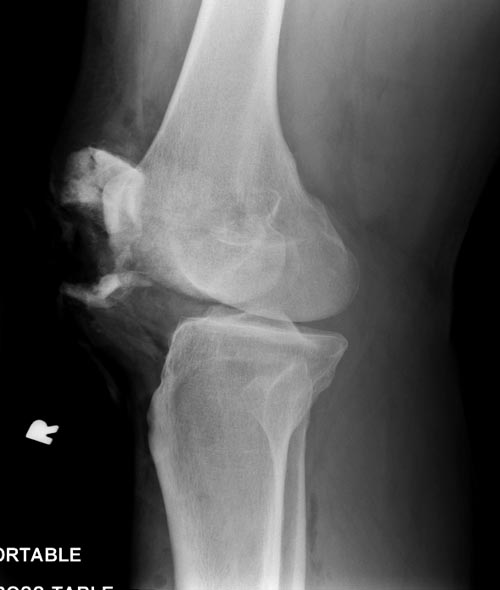

Посты: “Патологический перелом мыщелка бедра” и “Опухоль дистального метаэпифиза бедренной кости” идентичны, и это картина одного того заболевания, только в различных стадиях. Окончательный диагноз любого опухолевого процесса ставится на основании биопсии, а предварительный диагноз можно установить на основании рентгенологических данных.

С предварительным диагнозом отлично справляются рентгенологи, но в первом случае рентгенолог отписался “шаблонным” заключением, которое не помогло, и поэтому самому необходимо попытаться дифференцировать опухоль. В диагностике опухолей главным является возраст, где для каждой декады жизни характерны различные патологические состояния.

В возрасте между 20-40 годами из доброкачественных опухолей встречаются гигантоклеточные и энхондромы, а из злокачественных - только хондросаркома! Интенсивность и характер боли также имеет значение, например, усиление боли означает быстро растущую остеобластому, ГКТ или малигнизацию. Стрессовые и патологические переломы могут встречаться при злокачественном и при доброкачественном опухолях. Разрыв или вовлечение кортикального слоя означает метастазирование или стрессовый перелом. Четкие контуры показывает неагрессивную форму.

Второй случай, коллапс латерального мыщелка за счет стрессового перелома. До операции надо уточнить диагноз биопсией и определить границу поражения на КТ и МРТ. Здесь имеется вовлечение кортикального слоя и вряд ли дистракционный метод поможет восстановить контур мыщелка. Онкологический вариант замещения с удалением неплохой вариант, но агрессивный. Возраст молодой и при наличии костного банка можно было восстановить аллографтом. Сегодняшняя технология (3Д и КТ) позволяет подобрать идеальный размер целого мыщелка (аллографт).

Здесь представлен посттравматический дефект латерального мыщелка и лечение аллографтом.